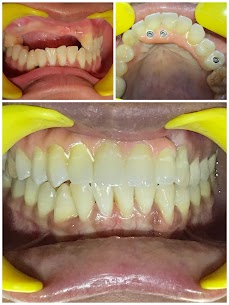

Implant Overdentures

- INFO:

Bar-supported overdentures for 68-year-old female with thin atrophied ridge